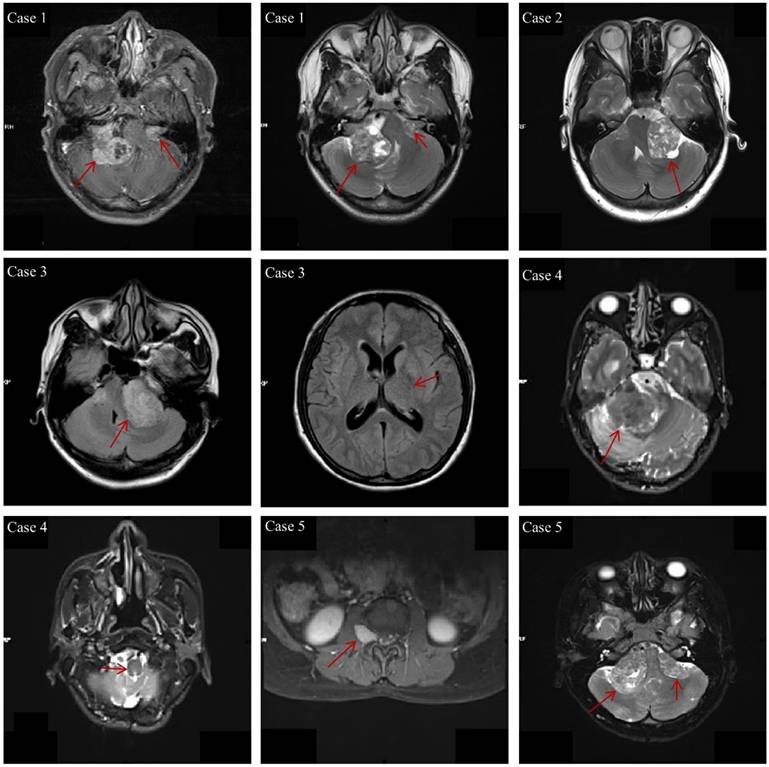

The clinical characteristics of the 29 NF2-SWN patients are listed in Table 2. The age of onset for almost all NF2-SWN patients was less than 40 years (93.1%), and most patients presented with tinnitus and hearing loss when visiting the hospital (72.4%). The majority of tumors were located in the cerebellar horn region (subtentorial, 96.7%), which is a primary cause of hearing loss among these patients. Furthermore, most patients exhibited multiple intracranial tumors (93.1%), with pathological results indicating that schwannomas were the most common tumor type (79.3%). Notably, patients with multiple tumors predominantly presented with a combination of schwannomas and meningiomas, which supports the second diagnostic criterion for NF2-SWN. Figure 1 demonstrates the typical radiological findings of intracranial tumors in NF2-SWN patients, including those with schwannomas combined with meningiomas.

Figure 1

The typical radiological findings of intracranial tumors in NF2-SWN patients. Case 1: Bilateral vestibular schwannomas; Case 2: Unilateral vestibular tumor, first-level relatives suffer from NF2-SWN; Case 3: Multiple meningiomas and unilateral vestibular schwannoma; Case 4: Heterozygous schwannomas (schwannoma and perineurium); Case 5: Vestibular schwannoma with intraspinal and subcutaneous masses.